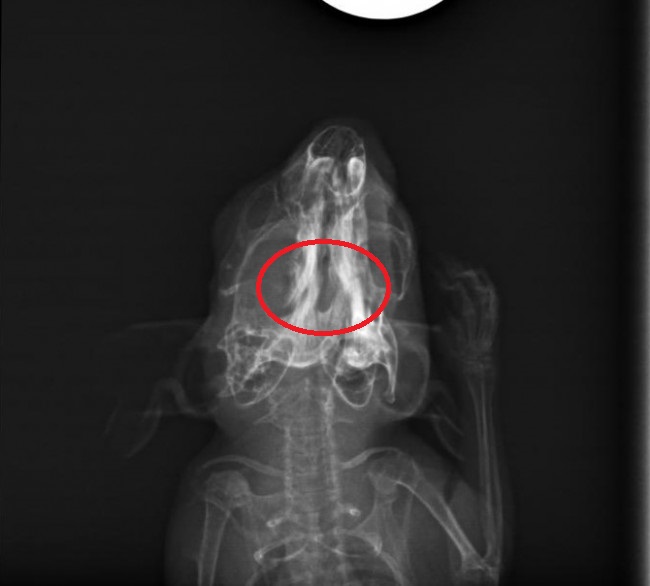

Die Röntgenbilder waren auch sehr Interessant anzusehen. Leider sieht man auf der seitlichen Aufnahme nicht sonderlich viel von dem Bruch, da sich der Knochen scheinbar nicht nach oben/unten verschoben hat.

Auf der anderen Aufnahme sah es für mich allerdings so aus, dass sich der Knochen auch ein Stück zur Seite verschoben hat. Die Bruchstelle hab ich mal eingekreist und für mich sieht es so aus, als ob die rechte und linke Hälfte des Kiefers betroffen sind.

- ida-rb1.jpg (42.79 KiB) 3020 mal betrachtet

@Viktor.K laut TA war / ist es auch ein doppelter Kieferbruch, deine Einkreisung könnte also stimmen